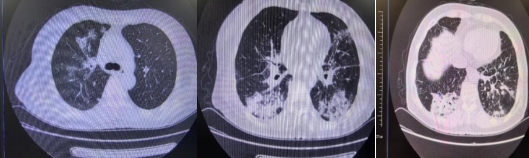

患者入院时胸部CT